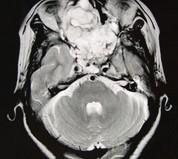

问题 女性,41岁,鼻腔流脓涕3年,鼻部面部肿胀1年,近来加重,MRI检查如图,请选择最可能诊断()

选项 A.鼻腔内囊肿 B.鼻腔内出血 C.鼻腔软骨瘤 D.鼻咽癌 E.鼻腔血管瘤

答案 C